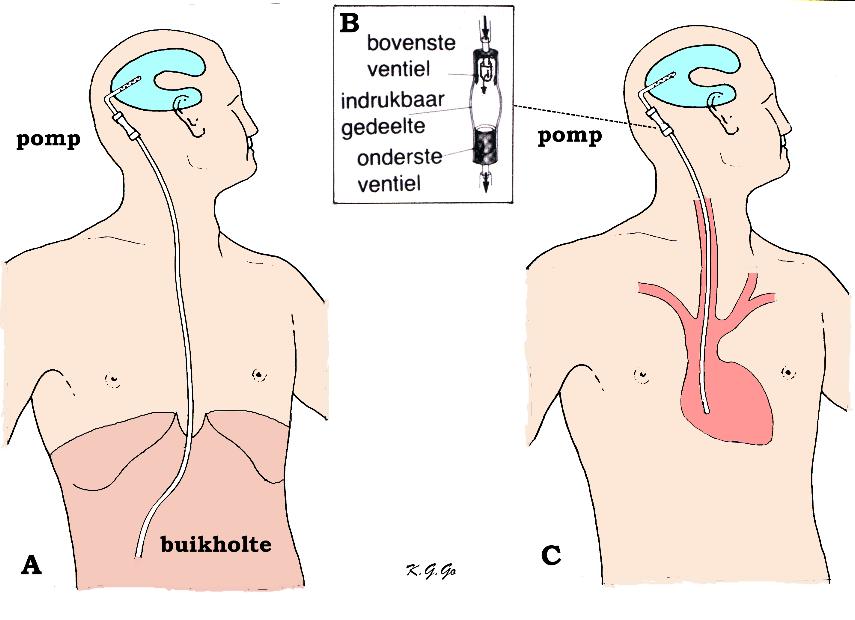

Вентрикуло-перитонеальный шунт: Показания и применение

Раздел: Фотоальбом решений